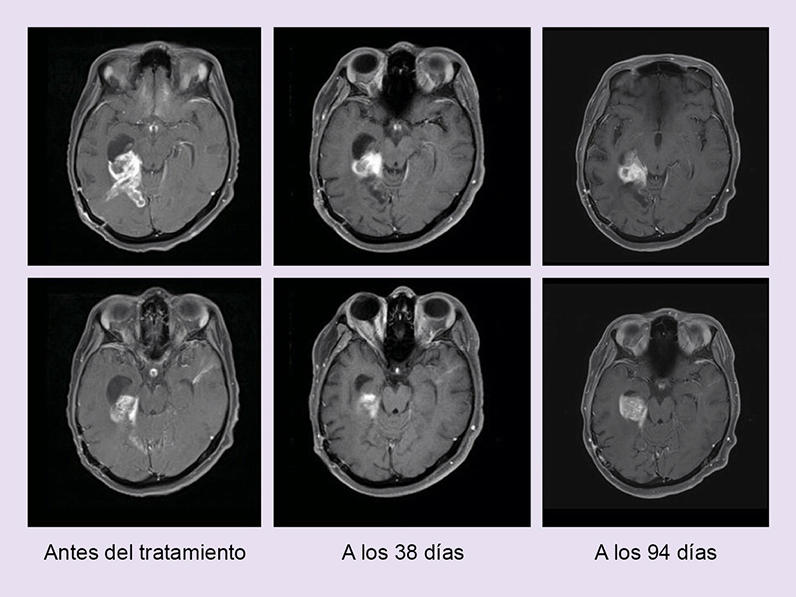

Imágenes por resonancia magnética de dos personas que tienen tumores de encéfalo con BRAF tratados con dabrafenib y trametinib (paciente 1, arriba; paciente 2, abajo).

Imágenes por resonancia magnética de dos personas que tienen tumores de encéfalo con BRAF tratados con dabrafenib y trametinib (paciente 1, arriba; paciente 2, abajo), en las que se observa que los tumores se achicaron al comienzo y luego volvieron a crecer.

En los pacientes con los tumores más comunes en estos estudios, las tasas de respuesta general fueron del 46 % para quienes tenían cáncer biliar, del 33 % para quienes tenían gliomas de grado alto y del 50 % para quienes tenían gliomas de grado bajo